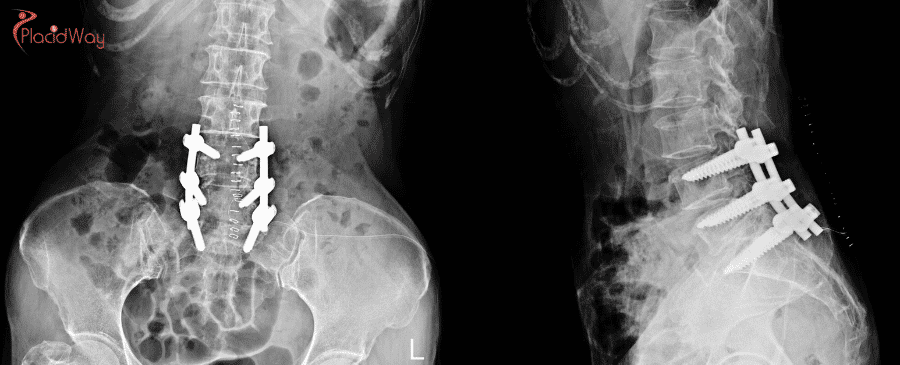

Additional Procedures (if needed): If a herniated disc is contributing to the stenosis, a discectomy (removal of the disc) may be performed. If removing the lamina makes the spine unstable, a spinal fusion may be necessary. This involves joining two or more vertebrae together with bone grafts and stabilizing them with screws and rods.